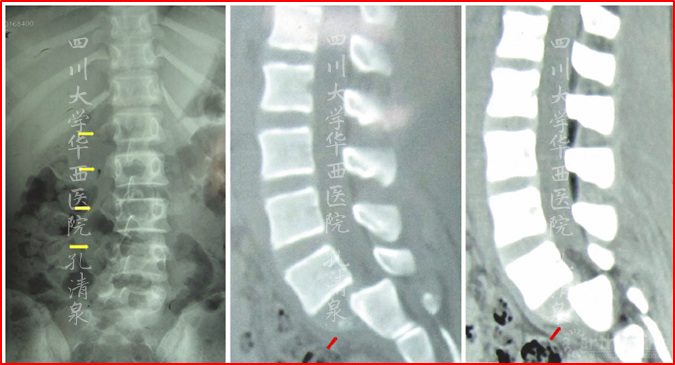

图8 腰椎正位像上示多节段腰椎右侧横突骨折,腰骶部侧凸,CT矢状面重建示腰5椎IV°滑脱,腰5骶1椎间盘完好,骶1前上缘骨骺向前滑移